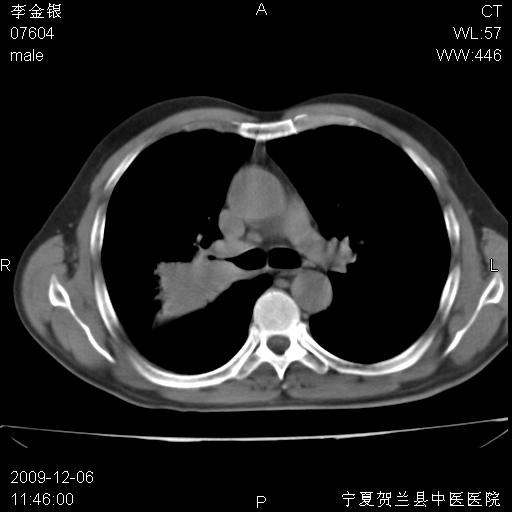

该病人 ,男,62岁,主因咳痰带血两天

考虑右肺中央型占位性病变并阻塞性肺炎.(右肺上叶支气管变窄),建议支纤镜检查.

支气管壁明显增厚 管腔狭窄,腔静脉后多个淋巴肿大,结合年龄病史考虑右肺上叶中央型肺癌并阻塞性肺炎

右肺上叶后段支气管阻塞,右上肺门占位,相应肺段阻塞性肺炎,右肺门有淋巴结肿大。诊断右肺上叶中心型肺癌,阻塞性肺肺炎、右肺门淋巴结转移。

符合中央型肺癌的ct表现并肺出血。但有一点腔静脉后有一钙化的淋巴结啊

右上叶支气管狭窄,管壁增厚,远端斑片状软组织影,病灶邻近叶间裂,叶间裂无移位。

诊断右肺中央型肺癌。

那个片影应该大部分都是病灶,病灶沿肺段支气管分支生长,后段完全显示不清、闭塞。若为不张应该伴有叶裂的移位,若为炎症应有空气支气管征。

右肺中心型肺癌伴阻塞性肺炎及右肺门与纵膈淋巴结转移很典型,可纤维支气管镜进一步检查

考虑右侧中央型肺癌伴右肺上叶后段阻塞性炎症、肺不张、右肺门和纵隔淋巴结肿大。